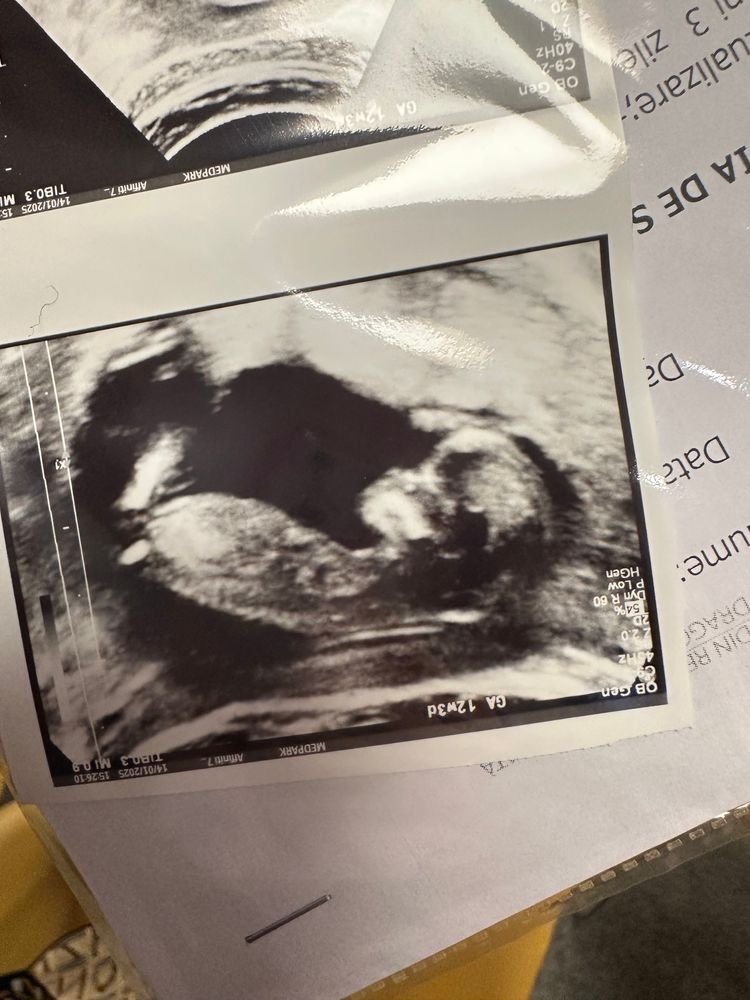

УЗИ скрининг - 12 недель

Результаты УЗИОх, я каждый раз смотрю на экран и не верю, что это со мной)) Такой человечек уже, копошится там что-то, зевает. Это настоящее чудо🙏🏼

По узи все хорошо, все параметры в норме.

Опережаем на 2 дня срок.